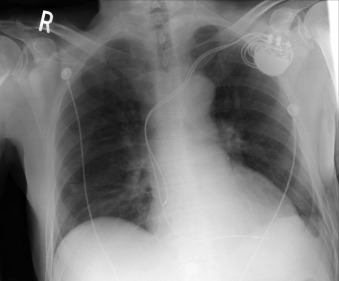

Chest radiography has a standard role in the identification of several potential complications such as pneumothorax, hemothorax, and several forms of malposition after insertion of pacemakers, implantable cardioverter defibrillators (ICDs), and cardiac resynchronization therapy devices.

Pacemaker leads are apparent, and ICDs are more obvious because of their larger coils. Coronary sinus leads for cardiac resynchronization therapy are finer leads.

Endocardial Pacer Leads

The position and integrity of endocardial pacer leads should be verified, especially when pacemaker dysfunction is clinically suspected ( Graphics 23-1 to 23-4 ; Figs. 23-1 to 23-15 ).The most common cause of pacemaker dysfunction that is apparent on the chest radiography is distal lead displacement/misplacement.

With a right atrial lead , the tip should be in the right atrial appendage.

With a right ventricular lead , the tip should lie anteriorly at the apex of the heart.